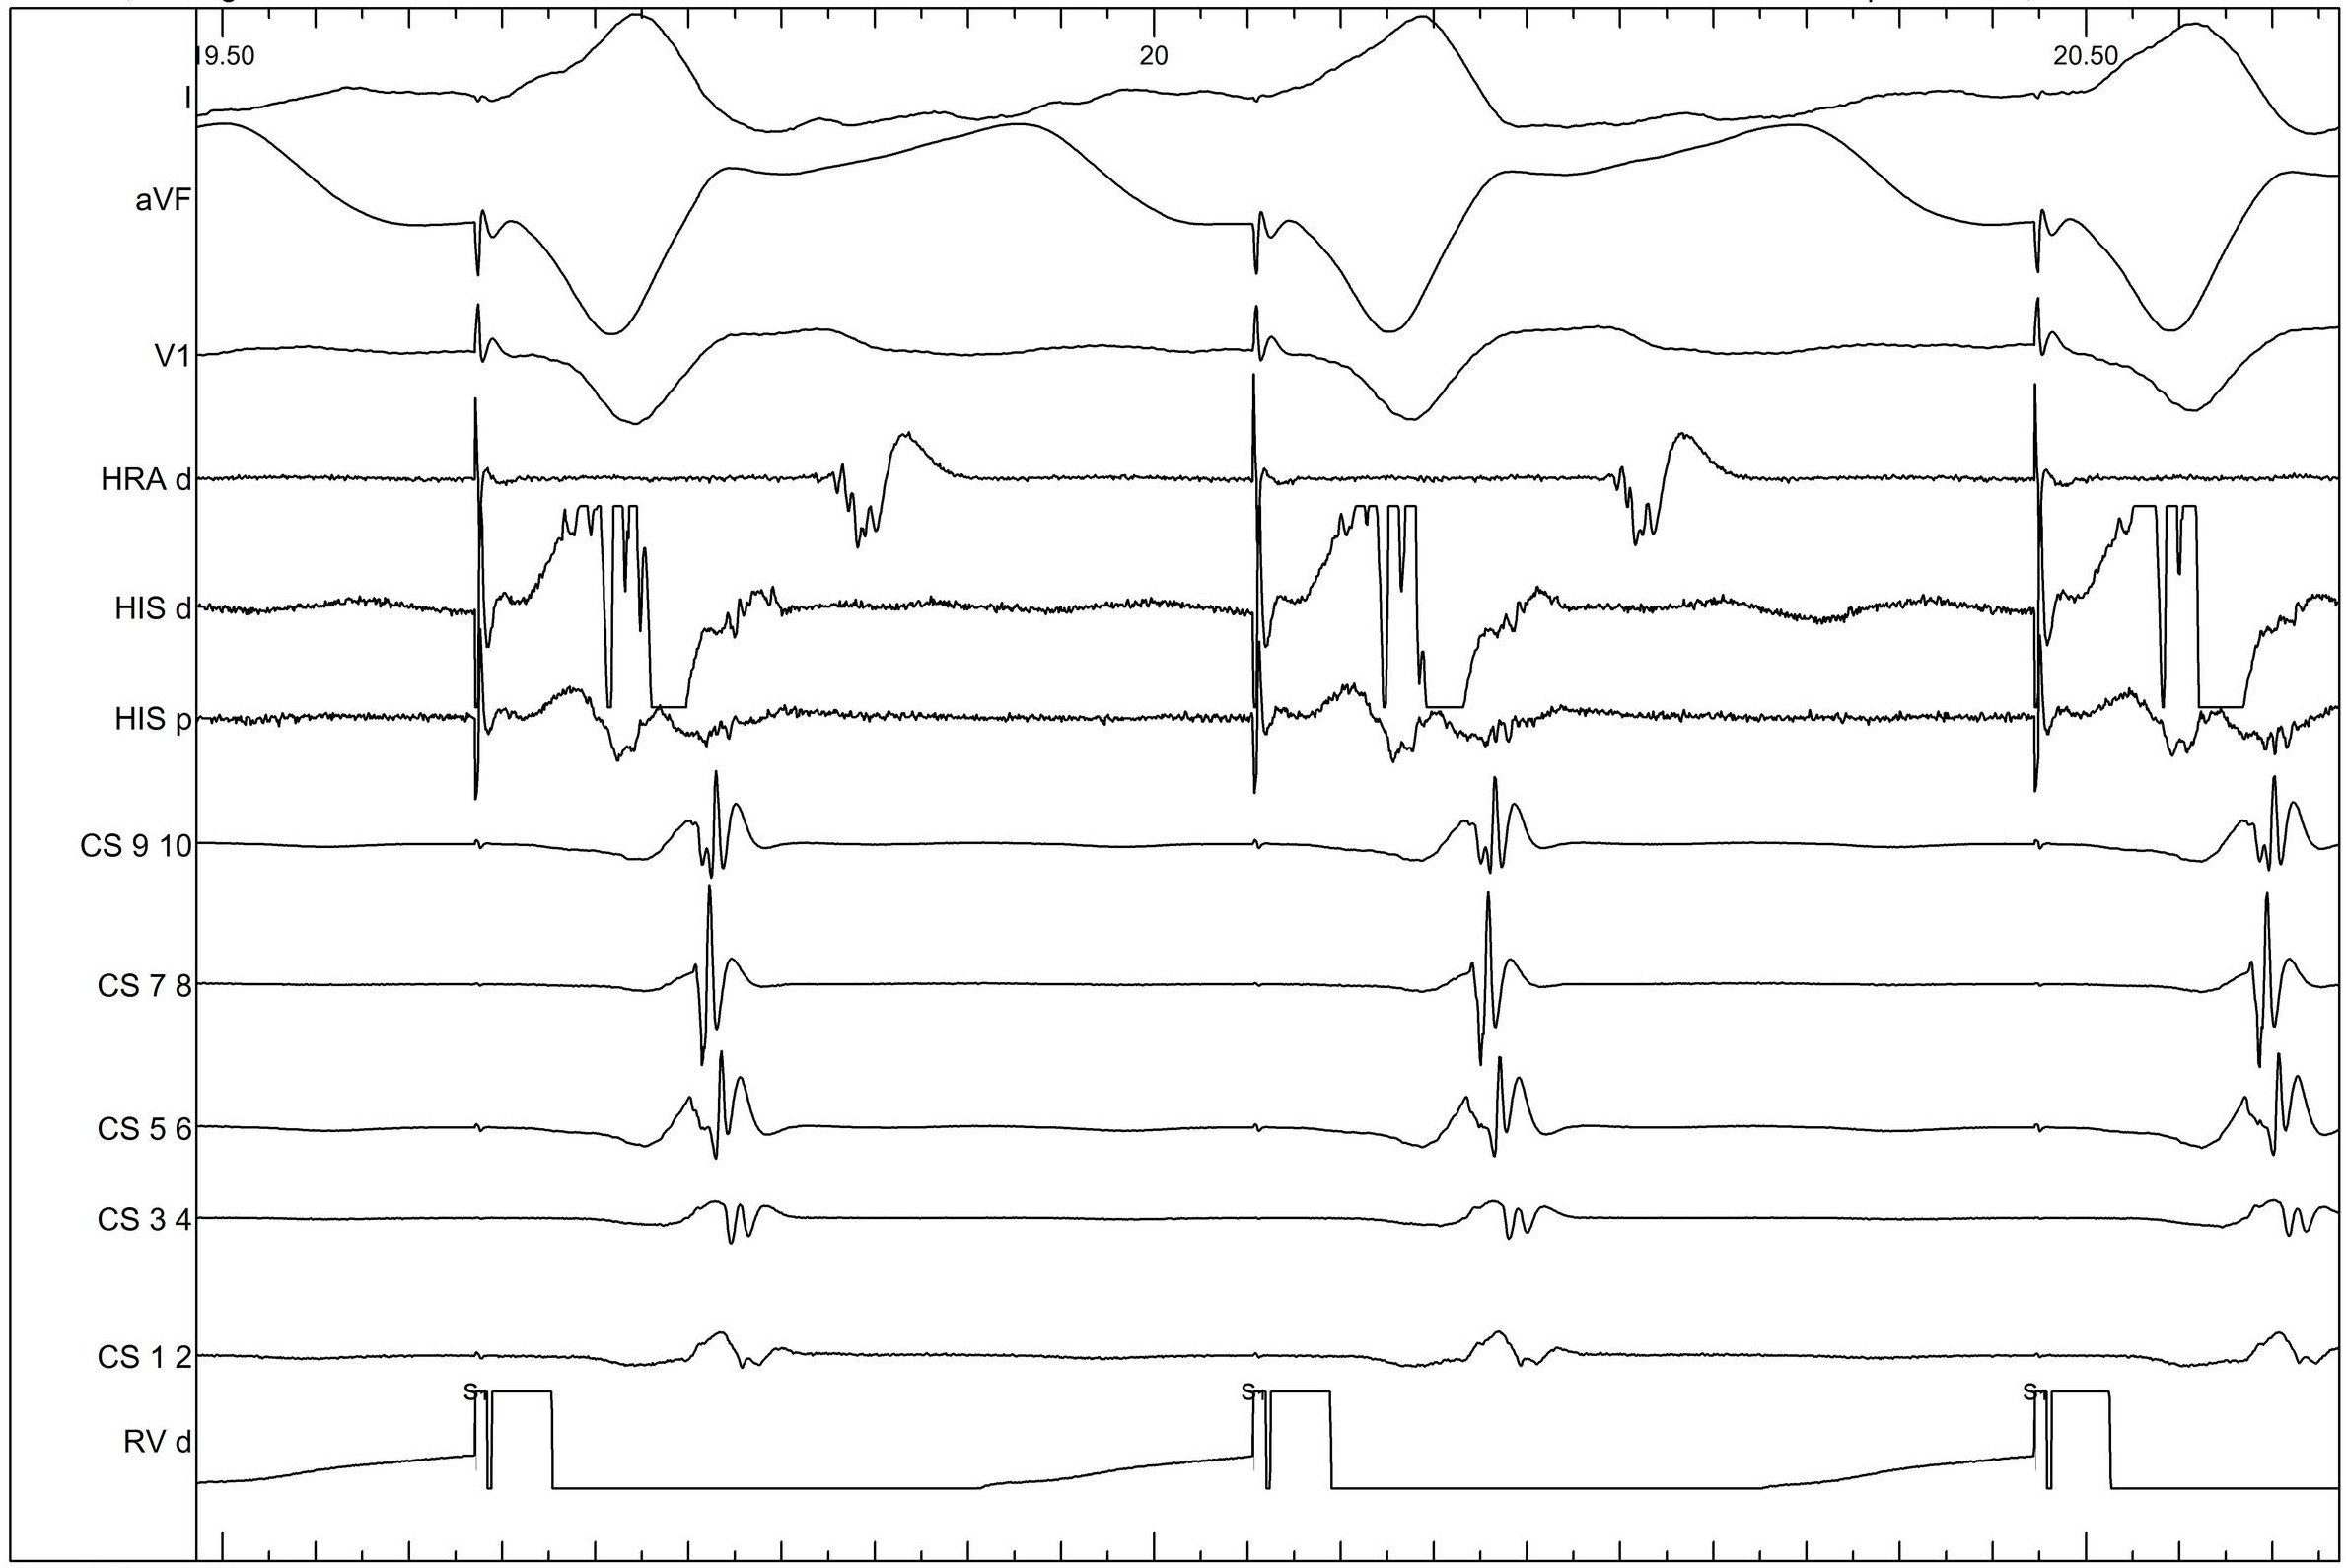

Ventricular pacing

02_vpace.jpg